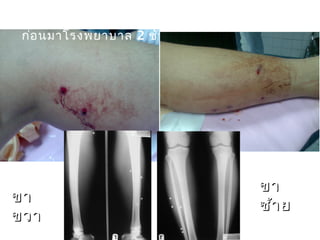

ชายไทยอายุ 21 ปี ถูกยิง 1 ครั้ง ที่ขา 2 ขา

ก่อนมาโรงพยาบาล 2 ชั่วโมง

ขาขา

ขวาขวา

ซ้ายซ้าย